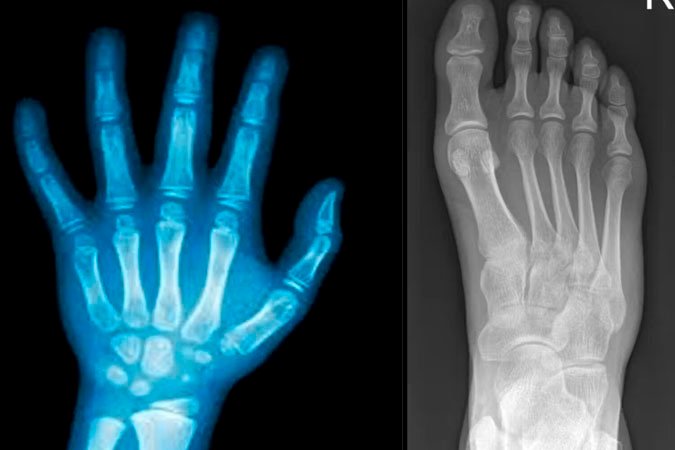

150 pessoas participaram dos testes clínicos, com resultados positivos em segurança e eficácia. Em um dos casos, uma fratura complexa de punho foi estabilizada em apenas três minutos com uma incisão de cerca de 2 a 3 centímetros, e após três meses o paciente recuperou a função sem complicações.

A cola para ossos quebrados pode ser usada em fraturas com múltiplos fragmentos até procedimentos ortopédicos e dentários, o que abre caminho para uma revolução nas cirurgias minimamente invasivas.